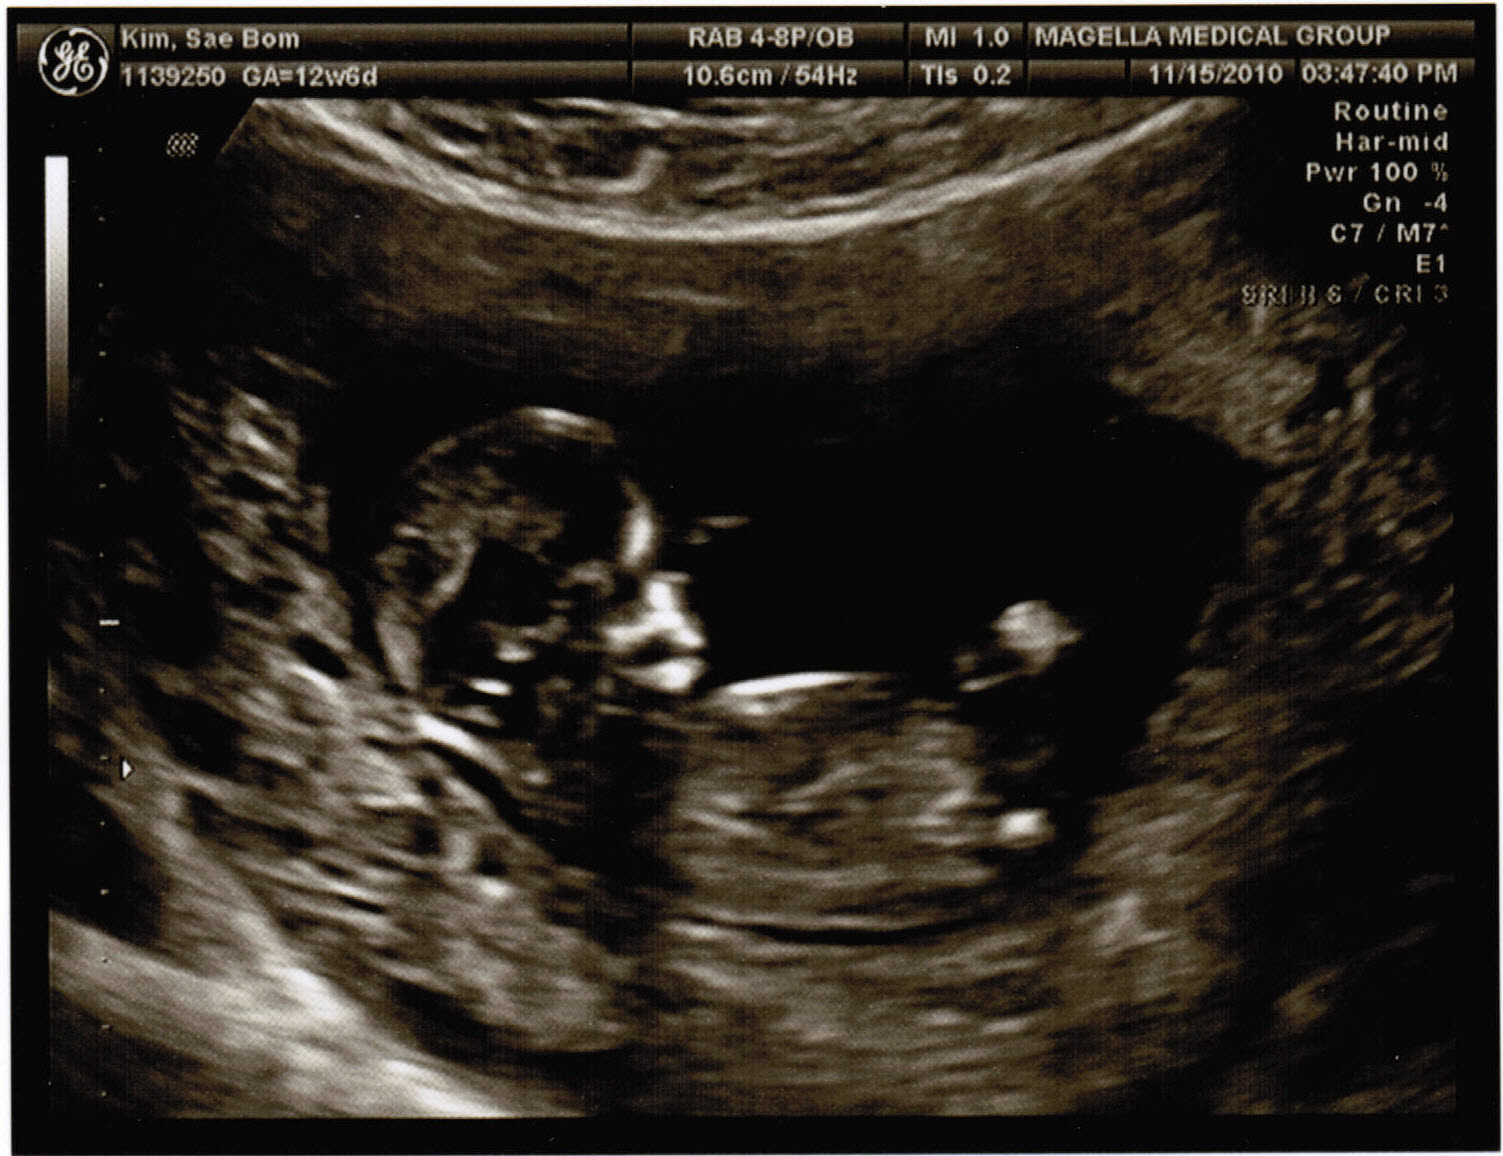

Okay so this is this second time we went to get the sonogram and have a clear shot of how it’s growing and if everything looks pretty normal. But i doubt they could really tell if anything was wrong at this point. Could they? I don’t know but once again i’m in awe just by hearing the heart beat alone. And to now see the full body inside Lisa just adds to the whole experience. I can’t wait!